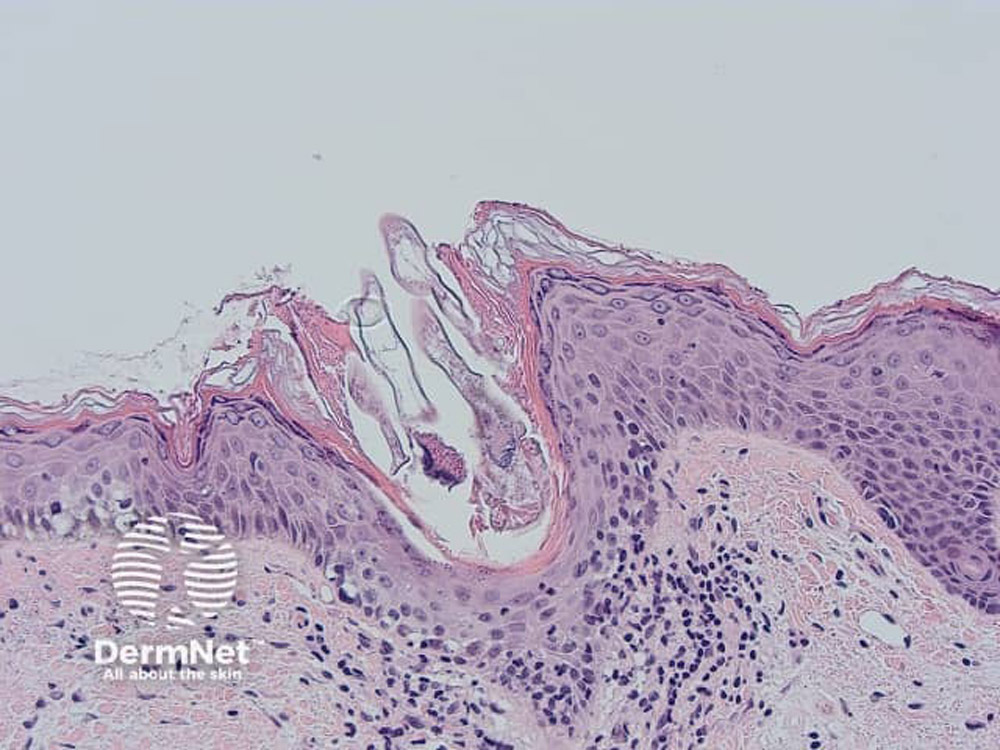

Image sourced from DermNet

Демодекоз – це дерматологічне захворювання паразитарної природи, яке пов’язане з надмірним розмноженням умовно-патогенного кліща Demodex (залозниці вугрової). За результатами наукових досліджень, кліщі цього роду можуть виявлятися у 80-90 % населення планети, проте клінічні прояви хвороби розвиваються не у всіх. У структурі шкірних покривів людини найчастіше паразитують такі кліщі: Demodex folliculorum та Demodex brevis. Вони мешкають у сальних залозах і волосяних фолікулах, споживаючи секрет сальних залоз та відмерлі клітини епідермісу.

Кліщ Demodex folliculorum має довжину приблизно 0,3-0,4 мм, а Demodex brevis – 0,15-0,2 мм. Життєвий цикл цих організмів триває кілька тижнів. Вони майже непомітні неозброєним оком і найбільш активні вночі: яскраве світло змушує їх заглиблюватися у волосяні фолікули, тоді як у темряві вони виходять на поверхню шкіри. Найчастіше кліщі локалізуються в ділянці повік (мейбомієвих залоз), на шкірі обличчя, у зоні надбрівних дуг, носогубних складках і на підборідді. Колонізація шкіри людини кліщем зазвичай починається ще в дитинстві – приблизно з 5-річного віку.

Основним методом лабораторної діагностики є мікроскопічне дослідження біоматеріалу, яке дозволяє візуально ідентифікувати самих паразитів, їхні яйця або окремі фрагменти структури кліщів за допомогою мікроскопа. [6]“Doverpress «The Association Between Acne Vulgaris, Acne Vulgaris with Nonspecific Facial Dermatitis, and Demodex Mite Presence»“